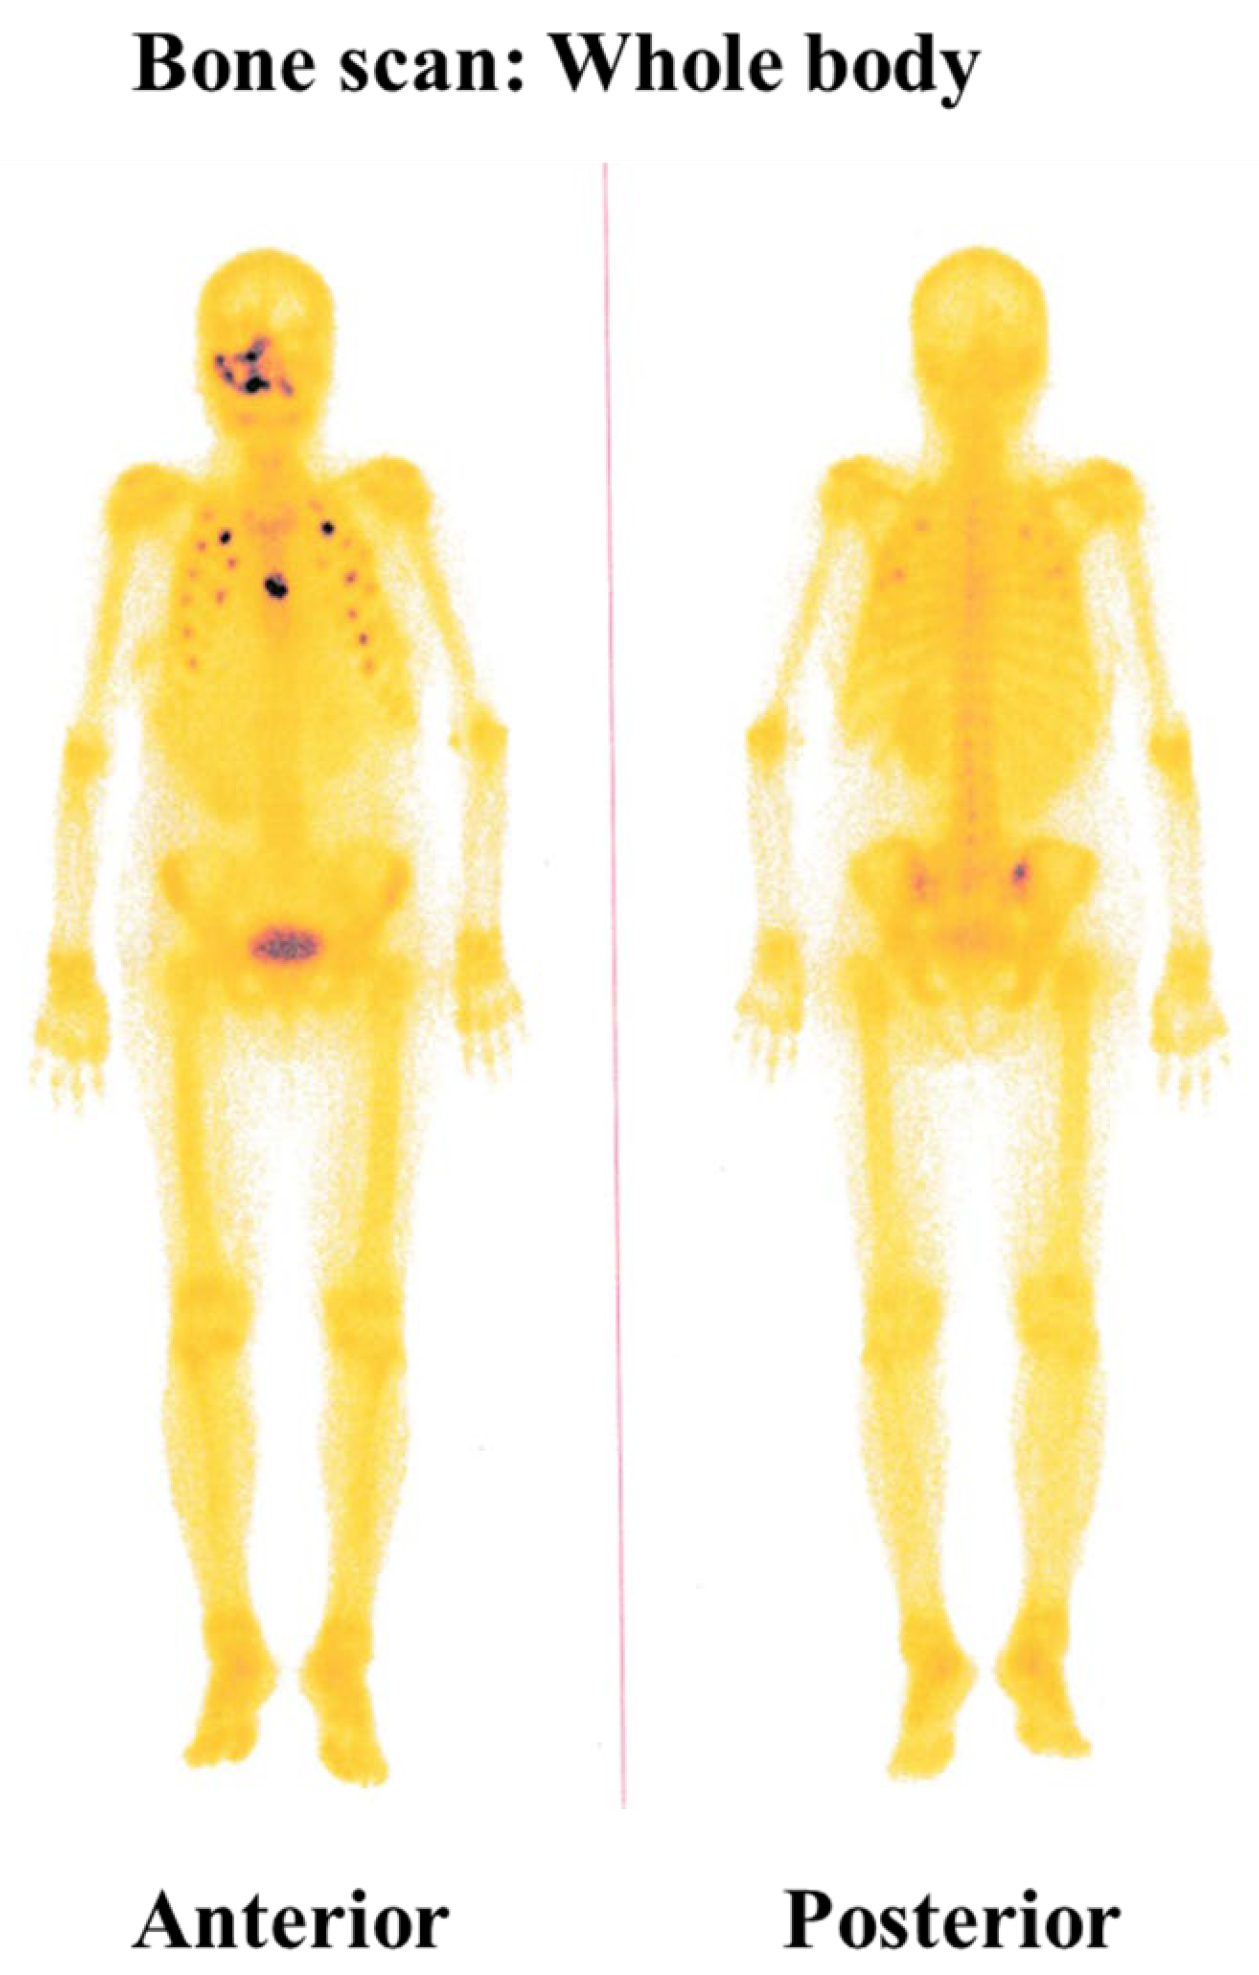

A CT urogram was conducted to investigate the patient’s overall condition further and evaluate potential metastatic involvement. The scan revealed a large, heterogeneous, mixed-density, calcified, enhancing mass lesion with central necrosis in the upper polar region of the right kidney posteriorly. The mass measured approximately 9.8 cm × 9.8 cm × 11.0 cm. Another heterogenous enhancing mass lesion was noted in the left adrenal region, measuring 4 cm × 4.2 cm × 6.6 cm. The size and characteristics of the right renal mass suggest it was the origin of the primary tumor (ccRCC), while the left adrenal mass appeared to be a secondary metastasis (Figure 2A,B). A chest CT scan was also performed, which revealed multiple pulmonary nodules in both lungs and mediastinal lymphadenopathy, suggesting secondary deposits (Figure 2C). Additionally, bone scintigraphy revealed multiple focal areas of increased radiotracer uptake in multiple ribs on both sides and the sternum, indicating that the disease had metastasized to the bones (Figure 3). These findings confirmed that the patient’s disease had spread systemically.

Figure 3.

Bone scintigraphy. Bone scintigraphy shows intense radiotracer concentration in the maxillofacial area. Additionally, multiple focal areas of increased radiotracer concentration are seen in several ribs and the sternum.